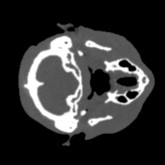

Cone-beam CT (CBCT) employs a flat-panel detector to achieve three-dimensional imaging with high spatial resolution. However, CBCT is susceptible to scatter during data acquisition, which introduces CT value bias and reduced tissue contrast in the reconstructed images, ultimately degrading diagnostic accuracy. To address this issue, we propose a deep learning-based scatter artifact correction method inspired by physical prior knowledge. Leveraging the fact that the observed point scatter probability density distribution exhibits rotational symmetry in the projection domain. The method uses Gaussian Radial Basis Functions (RBF) to model the point scatter function and embeds it into the Kolmogorov-Arnold Networks (KAN) layer, which provides efficient nonlinear mapping capabilities for learning high-dimensional scatter features. By incorporating the physical characteristics of the scattered photon distribution together with the complex function mapping capacity of KAN, the model improves its ability to accurately represent scatter. The effectiveness of the method is validated through both synthetic and real-scan experiments. Experimental results show that the model can effectively correct the scatter artifacts in the reconstructed images and is superior to the current methods in terms of quantitative metrics.